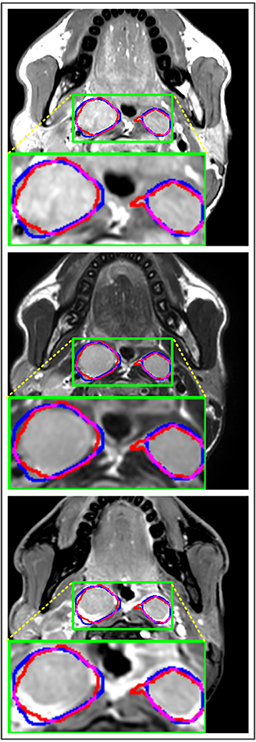

Comparison with ground truth. Some predicted results of MMFNet are shown in 2D images and 3D images in Figure 7 and Figure 8. As shown in these figures, although the shape and size of NPC are varied from each other, MMFNet can still accurately determine the regions of NPC and obtain the accurate contours of tumors. Through analyzing 2D images in figure 7, MMFNet has a capacity to fuse multi-modality MRI to reduce the confusion brought by intensity’ similarity between nearby tissues and NPC. The values of , and of MMFNet are shown in Table 1. MMFNet can reach the best results with , and .

Comparison with related works. Table 1 reports the values of , and for different methods. Predicted masks of different methods are illustrated in Figure 9 and Figure 10, which respectively present results in 2D and 3D images. Through comprehensively analyzing these results, the proposed MMFNet actually have the following properties:

(i) It directly fuses 3D MRI images rather than 2D slices. Thus, it can effectively use meaningful information from neighboring slices of MRI to realize NPC segmentation. As shown in Table 2, MMFNet can bring , and improvements in and compared to the best method based on 2D images (Multi-modality patch-based CNN). And Figure 10 shows that 3D-based methods have less isolated regions (false positives) than 2D-based ones.

(ii) It segments NPC by fusing multi-modality MRIs with the multi-encoder network. Thus, it can learn complementary and interdependent features from different modalities of MRI for final decisions. Additionally, comparing with input-level fusion networks and decision-level fusion networks, layer-level fusion networks (including MMFNet) can effectively capture informative features from different modalities of MRI and fuse low-level features and high-level features.

(iii) It uses a fusion block to fuse low-level features from different modalities of MRI and prepare these low-level features for the fusion with high-level features. Thus, it can more effectively fuse information from various sources. It also uses the self-transfer strategy to initialize the netwerk. Hereby, it can stimulate encoders to make full mining of meaningful features from modality-specific MRI. And it finally improve base multi-encoder-based network (Merging encoders’ fetures) by , and in and .